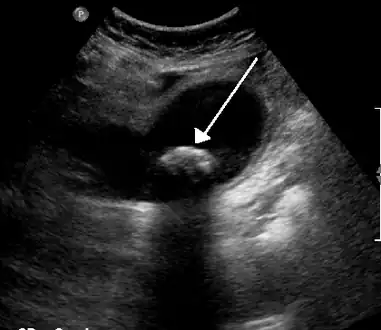

![]() | |

| Biliary colic is often related to a stone in the gallbladder | |

Diagnosis is guided by the person's presenting symptoms and laboratory findings. The gold standard imaging modality for the presence of gallstones is ultrasound of the right upper quadrant. There are many reasons for this choice, including no exposure to radiation, low cost, and availability in city, urban, and rural hospitals. Gallstones are detected with a specificity and sensitivity of greater than 95% with ultrasound.[18] Further signs on ultrasound may suggest cholecystitis or choledocholithiasis.[12] Computed Tomography (CT) is not indicated when investigating for gallbladder disease as 60% of stones are not radiopaque.[12] CT should only be utilized if other intra-abdominal pathology exists or the diagnosis is uncertain.[19] Endoscopic retrograde cholangiopancreatography (ERCP) should be used only if lab tests suggest the existence of a gallstone in the bile duct.[12] ERCP is then both diagnostic and therapeutic.